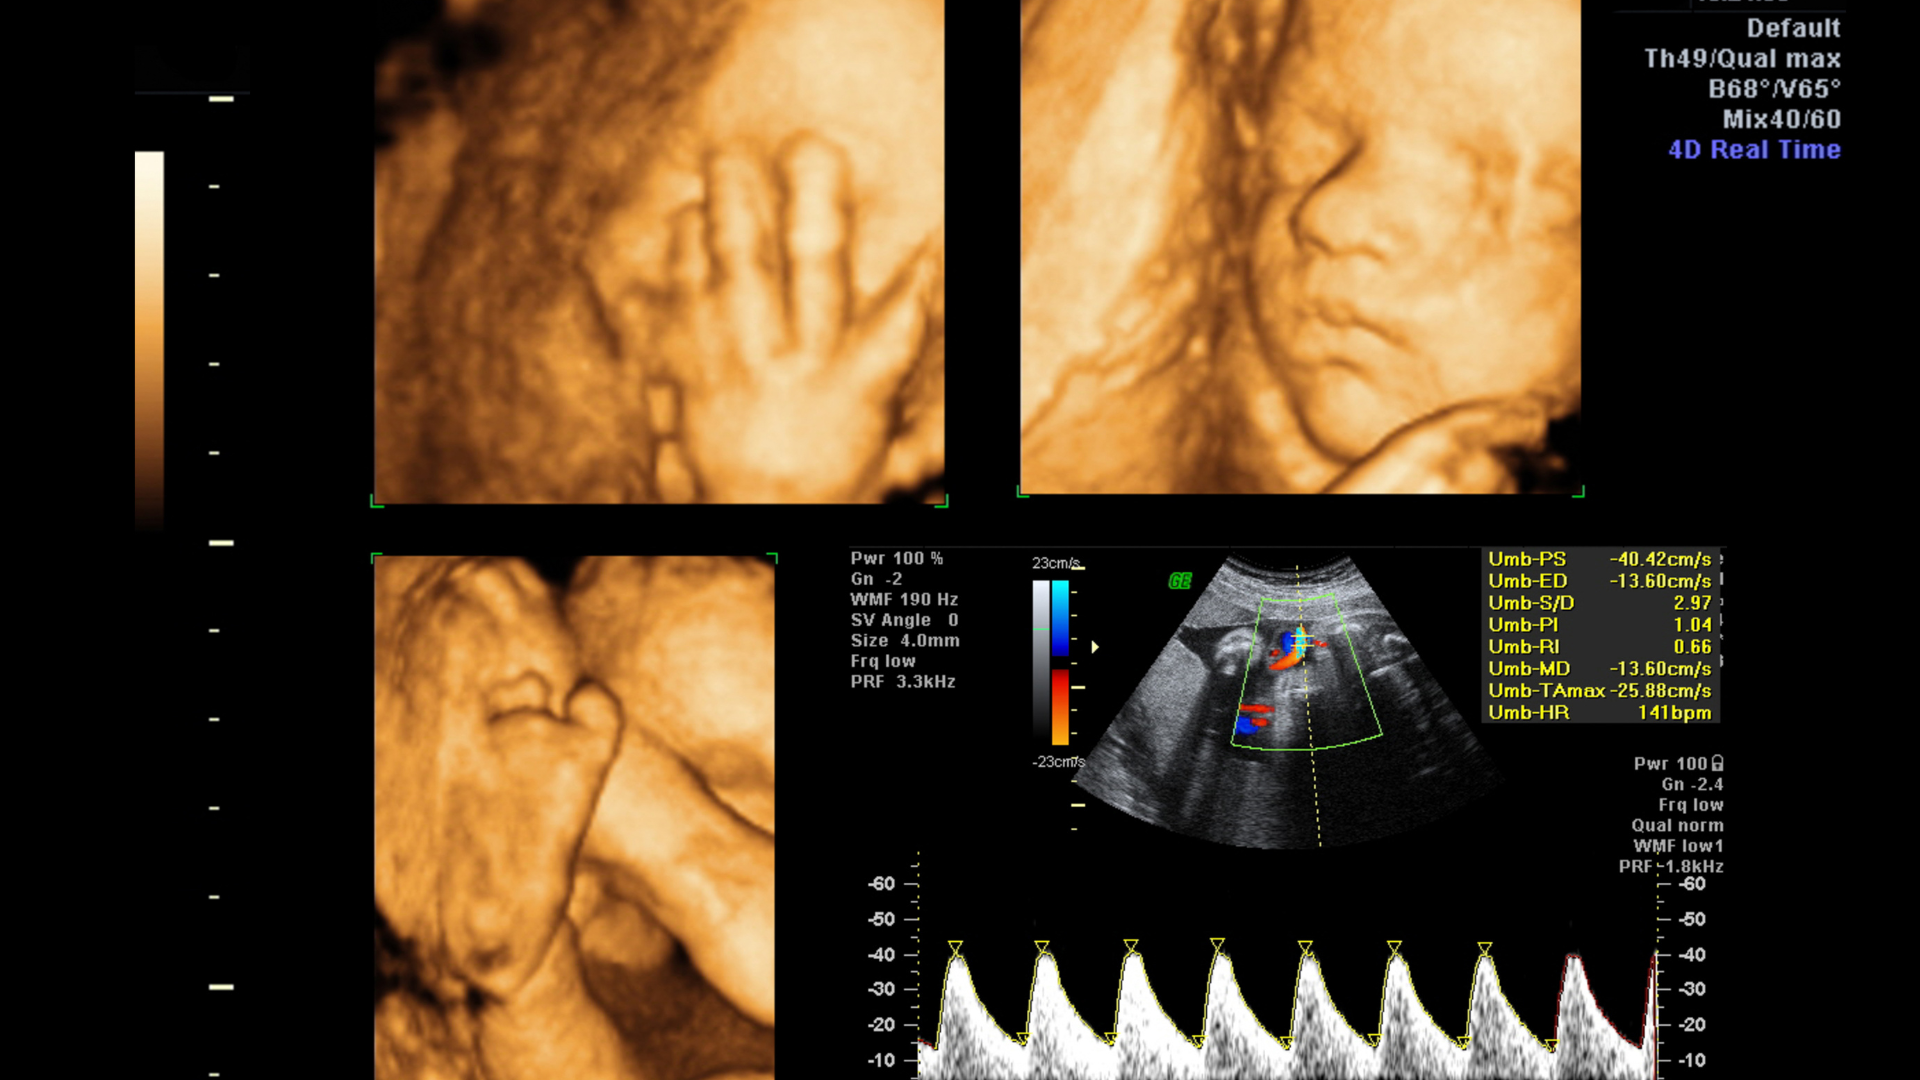

A 3D fetal scan creates three-dimensional images of your baby, allowing parents to see the baby’s facial features, limbs, and body structure. 4D scans add the element of motion, showing real-time movements like yawning, stretching, or kicking.

Unlike standard 2D ultrasounds that display black-and-white cross-sectional images, 3D & 4D fetal scans in Bangalore provide:

• Lifelike, high-resolution images of the baby

• Real-time visualization of movements

• Enhanced clarity for structural assessment

• 3D Imaging: Generates lifelike, three-dimensional images of your baby’s face, limbs, and body.

• 4D Imaging: Shows real-time movement, allowing you to watch your baby yawn, stretch, or kick.

Key Structures and Movements Observed in 3D & 4D Scans

During a 3D & 4D fetal scan in Bangalore, the sonographer evaluates:

• Face: Detecting cleft lip or palate and observing facial features.

• Limbs: Checking arms, legs, fingers, and toes for normal development.

• Spine and Skeletal System: Ensuring proper formation of vertebrae and bones.

• Movements: Observing kicks, stretches, yawns, and breathing-like motions.

• Placenta & Amniotic Fluid: Assessing the environment surrounding the baby for safety and growth.

• 2D Ultrasound: Standard grayscale imaging; useful for measuring growth, heartbeat, and basic anatomy.

• 3D Ultrasound: Generates three-dimensional static images; shows facial features and skeletal details.

• 4D Ultrasound: Adds the dimension of time, allowing real-time observation of fetal movements.

Top ultrasound centers in Bangalore offer cutting-edge technology for 3D & 4D scans:

• High-resolution imaging: Ensures clear visualization of fetal structures.

• Color Doppler: Monitors blood flow and detects any abnormalities in circulation.

• 3D/4D imaging: Lifelike, real-time images that enhance parental bonding.